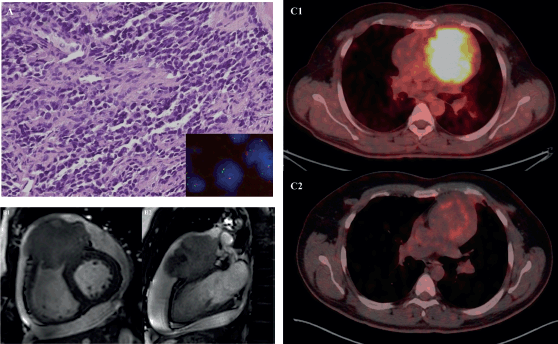

Figure 2. Histopathology of a 33-year-old female with cardiac synovial sarcoma synovial sarcoma – (a): Histological photomicrograph showing a spindle cell tumour with fascicular pattern of arrangement. (H&E 40×); (b): High power showing cells with spindled morphology with high N/C ratio with coarse chromatic and scanty cytoplasm. Mitosis can be noted. (H&E 200×); (c): IHC for TLE1 showing nuclear immunoreactivity; (d): FISH performed using break-part probes for SS18 gene showing spilt signals indicating SS18 gene rearrangement.

Figure 3. 31-year-old male with desmoplastic small round cell tumour arising from right ventricular outflow tract – (a): Histological photomicrograph showing a malignant round cell tumour with undifferentiated tumour cells with high NC ratio and scanty cytoplasm. (H&E 200×); FISH performed using fusion probes for Ewsr1-WT1 gene showing fused signals indicating EWSR1-WT1 fusion (Inset); (b): Cardiac MRI – short axis view (B1) and 2 chamber view (B2) showing expansile proliferative mass lesion involving the right ventricular outflow tract; (c): FDG PET-CT before (C1) and after (C2) 6 cycles of VAC chemotherapy.